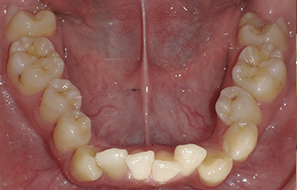

本院為40年 口腔外科專業診所,主攻”安全、無痛”、專拔高風險(牙根與神經交錯或緊貼)、高難度、深度阻生智齒手術。

外面一顆要拔兩個小時,本院一顆十分鐘

外面拔時易斷裂於骨頭內而難以取出